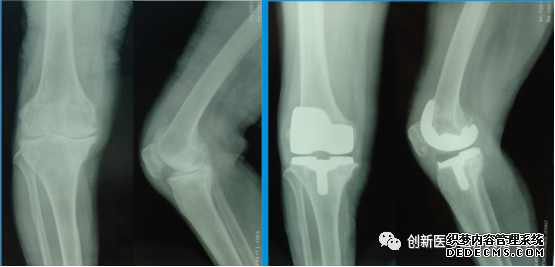

旋股内、外侧动脉的分支,是股骨头、颈的重要营养动脉。 股深动脉→旋股内侧动脉→骺外侧动脉供应股骨头2/3~4/5区域的血液循环,是股骨头最主要的供血来源。旋股内侧动脉损伤是导致股骨头缺血坏死的主要原因。 分类 1.按骨折线部位分类 (1)股骨头下骨折:易发股骨头缺血坏死。 (2)经股骨颈骨折:骨折线位于股骨颈中部,股骨头亦有明显供血不足,易发生股骨头缺血坏死,或骨折不愈合。 2.按骨折线方向分类 ①股骨颈外展骨折:Pauwel角<30°,骨折易愈合;②股骨颈内收骨折:Pauwel角>50° 外有小三,内人打我,婚姻不稳 临床表现 1.中、老年人有摔倒受伤史,伤后感髋部疼痛,下肢活动受限,不能站立和行走,应怀疑病人有股骨颈骨折。有时数天后发现。 2.患肢出现外旋畸形45°~60°之间。 若外旋畸形达到90°,应怀疑有转子间骨折。 3.可出现局部压痛及轴向叩击痛。 4.患肢短缩、大转子上移。在侧卧并半屈髋,由髂前上棘与坐骨结节之间画线,为Nelaton线(内拉东线),正常情况下,大转子在此线上,若大转子超过此线之上,表明大转子有向上移位。 治疗 1.非手术疗法 年龄过大,全身情况差,合并有严重心、肺、肾、肝等功能障碍不能耐受手术者,要尽早预防和治疗全身并发症,全身情况允许后尽早尽快手术治疗。可采用穿防旋鞋,下肢皮肤牵引,卧床6~8周。 2.手术治疗 股骨颈骨折以手术治疗为主 (1)闭合复位内固定术:是首选的手术方法。 (2)切开复位内固定术:适用于手法复位失败后固定不可靠,或青壮年陈旧骨折不愈合者。 (3)人工关节置换术:适用于全身情况尚好,GardenⅢ、Ⅳ型股骨颈骨折的老年患者。 表现:转子区出现疼痛,肿胀,瘀斑,下肢不能活动 查体:转子间压痛,下肢外旋畸形可达90°,有轴向叩击痛。下肢短缩。 治疗:稳定牵引 不稳定手术 临床表现 下1/3骨折 近端前上,远端向后。 有可能损伤腘动脉、腘静脉和胫神经、腓总神经 第二位容易休克的骨折(第一位为骨盆骨折)。 治疗 1.非手术疗法 (1)成人:麻醉下,在胫骨结节或股骨髁上进行骨骼牵引 持续牵引8~10周 (2)儿童:3岁以下儿童采用垂直悬吊皮肤牵引。 2.手术疗法 成人及三岁以上儿童股骨干骨折近年来多采用手术治疗。 (1)指征:①非手术疗法失败; ②同一肢体或其他部位有多处骨折; ③合并神经血管损伤; ④老年人的骨折,不宜长期卧床者; ⑤陈旧骨折不愈合或有功能障碍的畸形愈合; ⑥无污染或污染很轻的开放性骨折。 (2)手术治疗方法: ①切开复位,钢板螺钉内固定; ②带锁髓内钉内固定; ③弹性钉内固定; ④外固定架外固定。 治疗 必须坚持解剖复位、坚强固定,有骨缺损时应及时植骨填充。 1.胫骨干横切面呈三棱形,在中、下1/3交界处,变成四边形。 2.容易开放性骨折。 3.下1/3段骨折愈合较慢,容易发生延迟愈合或不愈合。 并发症 1.易发生创伤性关节炎。 2.胫骨上1/3骨折,可致胫后动脉损伤,引起下肢严重血循环障碍,甚至缺血坏死。 3.中1/3:骨筋膜室综合征 4.胫骨下1/3段骨折:骨不愈合。 5.腓骨骨折:腓总神经损伤,造成足下垂、趾背伸无力和足背外侧感觉障碍。 治疗 1.单纯胫骨干骨折采用手法复位,小夹板或石膏固定10~12周。 2.单纯腓骨干骨折,若不伴有关节分离,亦不需特殊治疗。可用石膏固定3~4周。 3.不稳定的胫腓骨干双骨折在以下情况时,采用切开复位内固定: ①手法复位失败; ②严重粉碎性骨折或双段骨折; ③污染不重,受伤时间较短的开放性骨折。 踝部骨折和踝部扭伤 踝关节是人体负重的主要关键 1.内侧副韧带 又称三角韧带,是踝关节最坚强的韧带。主要功能是防止踝关节外翻。 2.外侧副韧带 起自外踝,分三束分别止于距骨前外侧跟骨外侧和跟骨后方,是踝部最薄弱的韧带。 内人是坚强的后盾,防止外翻 外侧是最薄弱的韧带 1.压缩骨折:为最常见的脊柱骨折类型。 2.爆裂骨折:垂直型压缩性骨折,易截瘫 3.Chance骨折:为经椎体、椎弓及棘突的水平状撕裂性损伤,为不稳定性骨折,临床上比较少见。 4.Jefferson骨折:第一颈椎前、后弓双侧骨折 X线不易发现,CT清晰 影像学检查 1.X线正侧位摄片:是首选检查方法。 2.CT检查:可以显示出椎体的骨折情况 3.MRI检查:凡疑有脊髓、神经损伤 治疗 搬运:平托或整体滚动 脊柱手术指征: ①颈、胸、腰椎骨折脱位有关节突交锁; ②影像学检查有骨折碎片进入椎管内压迫脊髓; ③截瘫平面不断上升,提示有活动性出血者; ④手法复位不满意或存在脊柱不稳定。 骨盆骨折 1.常伴有严重多发伤,见有血压低、休克等。 2.骨盆骨折的主要体征: (1)骨盆分离试验与挤压试验阳性(题眼) (2)肢体长度不对称 (3)会阴部的瘀斑是耻骨和坐骨骨折的特有体征 常见并发症 1.腹膜后血肿 可以迅速致死。(不切开) 2.盆腔内脏损伤 诊断性腹腔穿刺吸出不凝血可考虑有内脏损伤。 3.膀胱与后尿道、直肠损伤损伤 血尿者考虑合并尿道、膀胱或肾的损伤。 4.脂肪栓塞与静脉栓塞 前脱位最多见 其他关节脱位均为后脱位多见 临床表现 1.方肩畸形:检查可发现患肩呈方肩畸形,肩胛盂处有空虚感,上肢有弹性固定。 2.Dugas征阳性:有脱位时将患侧肘部紧贴胸壁时,手掌搭不到健侧肩部,或手掌搭在健侧肩部时,肘部无法贴近胸壁,称Dugas征阳性。 治疗:手法复位 一般采用局部浸润麻醉,用足蹬法(Hippocrates法)复位。 复位后三角巾选吊周。 1.多发生在5岁以下的儿童 2.儿童的腕、手有被向上的牵拉受伤历史。 3.肘部疼痛受限 4.治疗 不用麻醉即可进行手法复位。 复位后不必固定。 1.后脱位最为常见。乘车跷二郎腿易发生 呈屈曲、内收、内旋畸形。(后内内) 大转子上移 2.前脱位典型表现 患肢呈屈曲、外展、外旋畸形。腹股沟处肿胀,可摸到股骨头。 治疗 复位宜早,最初24~48小时是复位的黄金时期 常用的复位方法Allis法(提拉法) 复位后用绷带将双踝暂时捆在一起 打篮球起跳损伤半月板,落地损伤前交叉。 走(轴移)厕(侧方应力)所拉(Lachman)抽(抽屉试验) 侧方应力为检查侧副韧带,其余均为检查交叉韧带。 1.侧方应力试验 在膝关节完全伸直位与屈曲30°位置下做被动膝内翻与膝外翻动作,并与对侧作比较。如有疼痛或发现内翻外翻角度超出正常范围并有弹跳感时,提示有侧副韧带扭伤或断裂。提示有侧副韧带扭伤或断裂。 2.抽屉试验 建议在麻醉下进行操作。膝关节屈曲90°,小腿垂下,检查者用双手握住胫骨上段做拉前和推后动作,并注意胫骨结节前后移动的幅度。 前移增加表示前交叉韧带断裂; 后移增加表示后交叉韧带断裂。 3.轴移试验 本试验用来检查前交叉韧带断裂后出现的膝关节不稳定。患者侧卧,检查者站在一侧,一手握住踝部,屈曲膝关节到90°,另一手在膝外侧施力,使膝处于外翻位置,然后缓慢伸直膝关节,至屈曲20°~30°位时觉疼痛与弹跳,是为阳性结果。提示前外侧旋转不稳定。 4.Lachiman试验 比抽屉试验阳性率高 MRI检查可以清晰地显示出前、后交叉韧带的情况。(首选) 半月板内侧程C 外侧O 检查方法:伸屈挤磨蹲 1.过伸试验 2.过屈试验 3.半月板旋转挤压试验 4.研磨试验 5.蹲走试验 首选MRI 半月板撕裂治疗:首选关节镜。 1.一般应争取在伤后6~8小时内进行。 2.手部创伤止血带缚于上臂上1/3处。 3.则应采用干燥冷藏法保存,即将断肢用无菌或清洁敷料包好,放入塑料袋中,再放在加盖的容器内,外周加冰块保存。但不能让断肢与冰块直接接触,以防冻伤,也不能用任何液体浸泡。 4.到达医院后,立即检查断肢,用无菌敷料包好,放在无菌盘上,置入4℃冰箱内。 5.若为多个手指,应分别予以标记 6.上臂和大腿离断,时限须严格控制,断指对全身影响小,则可延长至12~24小时。 断肢(指)再植的禁忌证 (1)患全身性慢性疾病,或合并严重脏器损伤,不允许长时间手术,或有出血倾向者。 (2)断肢(指)多发性骨折及严重软组织挫伤,血管床严重破坏,血管、神经、肌腱高位撕脱者。 (3)断肢(指)经刺激性液体及其他消毒液长时间浸泡者。 (4)在高温季节,离断时间过长,断肢未经冷藏保存者。 (5)病人精神不正常,本人无再植要求且不能合作者。 中(正中N)原(猿手)迟(尺N)早(爪形手)闹(桡N)炊烟(垂腕) 1.桡神经 垂腕”状态,各手指掌指关节不能背伸,拇指不能伸,前臂旋后障碍 手臂桡侧皮肤感觉减退或消失。感觉障碍以第1、2掌骨间隙背面“虎口区”皮肤最为明显。 2.尺神经损伤 肌肉:骨间肌、蚓状肌、拇收肌麻痹所致的第4、5指的指间关节弯曲,称为“爪形手”畸形 运动:手指内收(夹纸试验阳性)、外展障碍和Froment征 感觉:手部尺侧半和尺侧一个半手指感觉障碍。 3.正中神经损伤 前臂不能旋前,屈腕无力,拇、示指、中指不能屈曲,拇指不能对掌,鱼际肌萎缩,手掌平坦,称为“猿手”。 感觉障碍以拇指、示指和中指的末节为明显。亦可见明显的血管收缩和营养障碍。 1.坐骨神经损伤 髋关节后脱位、臀部刀伤、臀肌挛缩手术伤以及臀部肌注药物均可致其高位损伤 (1)股后部肌肉及小腿和足部所有肌肉全部瘫痪,导致膝关节不能屈、踝关节(屈伸)与足趾运动功能完全丧失,呈足下垂。 (2)小腿后外侧和足部感觉丧失,足部出现神经营养性改变。 2.腓总神经损伤 (1)腓总神经易在腘部及腓骨小头处损伤 (2)踝背伸、外翻功能障碍,呈内翻下垂畸形。以及伸踇、伸趾功能丧失,呈屈曲状态 1.本病有自限性,一般在6~24个月左右可自愈 2.发病年龄50岁左右,女性多于男性。左侧多于右侧3.肩周痛以肩袖间隙区、肱二头肌长腱压痛为主。 4.肩各方向主动、被动活动均不同程度受限。 5.X线片见肩关节结构正常。MRI见关节囊增厚,当厚度>4mm对诊断本病的特异性达95%。 治疗 1.早期给予理疗、针灸、适度的推拿按摩 2.痛点局限时,可局部注射醋酸泼尼松龙。 3.短期服用非甾体抗炎药 4.应每日进行肩关节的主动活动。 5.以上治疗无效时,在麻醉下采用手法或关节镜松解粘连,然后再注入类固醇或透明质酸钠,可取得满意疗效。 伸肌腱牵拉试验(Mills征):伸肘,握拳,屈腕,然后前臂旋前,此时肘外侧出现疼痛为阳性。有时疼痛可牵涉到前臂伸肌中上部。 治疗 1.限制用力握拳、伸腕:治疗和预防复发的关键。( 2.首选封闭,制动压痛点可采用局部药物行封闭治疗,只要注射准确,均能取得极佳的近期效果。疗效是否巩固,与能否适当限制腕关节活动关系很大。这是肱骨外上髁炎首选的治疗方法。 1.弹响指、弹响拇 2.各手指发病的频度依次为中、环指最多,示、拇指次之,小指最少。 3.疼痛常在近侧指间关节,而不在掌指关节。 4.体检时可在远侧掌横纹处扪及黄豆大小的痛性结节,屈伸患指该结节随屈肌腱上、下移动,或出现弹拨现象,并感到弹响即发生于此处。 5.儿童拇长屈肌腱鞘炎常为双侧 6.桡骨茎突狭窄性腱鞘炎:握拳尺偏腕关节时,桡骨茎突处出现疼痛,称Finkelstein试验阳性。 治疗 1.局部制动和局部封闭 2.非手术无效,腱鞘切开减压术 Dugas症. Froment症 Thomas症 Mills症 Finkelsein症 1.创伤性因素 2.非创伤性因素 ①长期应用激素;②乙醇中毒;③减压病;④镰状细胞贫血;⑤特发性股骨头坏死。 临床表现 最先出现的症状为髋关节或膝关节疼痛 髋关节活动受限,其中以内旋转及外展活动受限最为明显。 “4”字试验阳性 影像学 (1)X线检查:普通X线片为常规检查手段 I期溶解透明带(形成新月征) Ⅱ期修复硬化带 Ⅲ期塌陷 Ⅳ脱位。 (2)磁共振成像(MRI):是一种有效的非创伤性的早期诊断方法,可见“双线征” (3)计算机断层扫描(CT)CT三维重建图像可以更好地评价股骨头的变性和塌陷程度。 (4)放射性核素扫描:对于股骨头缺血性坏死的早期诊断具有很大价值 治疗 1.非手术治疗 严格避免持重 2.手术治疗 (1)髓芯减压术 (2)带血管蒂骨移植 (3)关节置换术:对于髋白和股骨头均受累、出现骨关节炎的表现、明显影响病人生活质量者可考虑行全髋关节置换术。 颈椎病的分型 1.神经根型颈椎病 发病率最高 临床上开始多为颈肩痛,短期内加重,并向上肢放射 上肢牵拉试验(Eaton试验/伊顿)阳性 压头试验(Spurling试验)阳性 2.脊髓型颈椎病 临床表现为上肢或下肢麻木无力、僵硬、双足踩棉花感,足尖不能离地,上肢无力、持物不稳。 后期可出现尿频或排尿、排便困难等大小便功能障碍。 病理阳性 3.交感神经型颈椎病 交感神经兴奋症状。如头痛,头晕;视物模糊、视力下降,瞳孔扩大或缩小,眼后部胀痛;心跳加速、心律不齐,心前区痛和血压升高;头颈及上肢出汗异常以及耳鸣、听力下降,发音障碍等。 4.椎动脉型颈椎病 眩晕、猝倒、头痛、视觉障碍 治疗 1.非手术治疗 (1)颈椎牵引:适用于脊髓型以外的各型颈椎病。 颈部理疗 、自我保健 (2)脊髓型 手术 ①颈椎前路减压融合术 ②后路减压术 腰椎间盘突出症是引起腰腿疼的最常见原因, 病因:椎间盘退变。 腰4~5、腰5~骶1间隙发病率最高。 临床表现 1.腰痛 最早 2.坐骨神经痛 典型坐骨神经痛是从下腰部向臀部、大腿后方、小腿外侧直到足部的放射痛。患者在喷嚏或咳嗽时由于增加腹压而使疼痛加剧。 3.马尾综合征 :大小便障碍(手术指征) 4.腰椎侧凸 5.直腿抬高试验(Lasegue试验)及加强试验 6.神经系统表现 (1)腰5/L5受累(L4-5椎间盘突出): 感觉:小腿外侧和足背痛、触觉减退; 肌力:拇趾背伸力下降; (2)骶1/S1神经根受压(L5-S1椎间盘突出) 感觉:外踝附近及足外侧痛、触觉减退。 肌力:足跖屈力减弱 反射:踝反射减弱或消失表示骶1神经根受压 记忆:我真背(L5拇指背屈无力、足背痛) 第一(S1)只曲(跖屈)子坏(踝反射)了 辅助检查 (1)X线平片 单纯X线平片不能直接反映是否存在椎间盘突出。 (2)CT和MRI CT可显示骨性椎管形态,黄韧带是否增厚及椎间盘突出的大小、方向等,对本病有较大诊断价值,目前已普遍采用。 MRI可全面地观察各腰椎间盘是否病变,也可在矢状面上了解髓核突出的程度和位置,并鉴别是否存在椎管内其他占位性病变。 治疗 非手术治疗主要适应于: ①年轻、初次发作或病程较短者; ②休息后症状可自行缓解者; ③由于全身疾病或有局部皮损,不宜手术者或不同意手术者。 手术治疗 (1)手术治疗适应证: ①腰腿痛症状严重,反复发作,半年以上非手术治疗无效,病情加重影响工作生活者; ②中央型突出有马尾神经综合征,括约肌功能障碍者③明显神经受累表现者。 (2)手术方法:全椎板切除髓核摘除术、半椎板切除髓核摘除术、显微外科腰椎间盘摘除术、微创椎间盘切除、人工椎间盘置换术 多见于50岁以上的中老年人,女性多于男性。好发于负重较大的膝关节、髋关节、脊柱及远侧指间关节等部位,不累及腕关节,该病亦称为骨关节病、退行性关节炎、增生性关节炎等。 年龄是主要高危因素,其他因素包括外伤、肥胖、遗传、炎症、代谢等。软骨变性是OA最基本的病理改变。 临床表现 1.关节疼痛及压痛 2.关节僵硬 晨起时关节僵硬及发紧感,活动后缓解,在气压降低或空气潮湿时加重,持续时间较短,很少超过30分钟。(此可与类风湿性关节炎晨僵加以鉴别) 3.关节肿大 手指远侧指间关节侧方增粗,形成Heberden结节和Bouchard结节。部分膝关节可因骨赘形成及关节积液而肿大。 4.骨擦音(感)关节软骨破坏、关节面不平 辅助检查 1.X线检查 非对称性关节间隙变窄,软骨下骨硬化和(或)囊性变,关节边缘增生和骨赘形成,或伴有不同程度的关节积液,部分关节内可见游离体,严重者出现关节畸形,如膝内翻。 治疗 1.非药物:减少不合理运动 2.药物疗法 (1)控制症状药物 首选对非甾体抗炎药。乳胶剂、体积、膏剂首选。 (2)改善病情药物及软骨保护剂 透明质酸、氨基葡萄糖、硫酸软骨素、双醋瑞因等。 (3)关节腔内注射糖皮质激素:4-6周非甾体无效,炎症明显,一年不超3-4次。 3.手术疗法 手术方法: 游离体摘除 关节镜下关节清理术 截骨术 关节融合术和关节成形术 晚期:人工关节置换术。 第一位:金黄色葡萄球菌:最常见 第二位:乙型溶血性链球菌 感染途径:血源性播散 临床表现 1.儿童多见,以胫骨上段和股骨下段最多见 2.起病急骤。有寒战,继而高热至39℃以上,有明显的毒血症症状。 3.早期只有患区剧痛,肢体半屈曲状,周围肌痉挛,因疼痛抗拒做主动与被动运动。 4.维持3~4周。脓肿穿破后疼痛即刻缓解,→窦道,转入慢性阶段。 辅助检查 1.血常规 WBC↑,中性↑ CRP↑ 2.血培养 在寒战高热期抽血培养或初诊时每隔2小时抽血培养一次,共三次,可以提高血培养阳性率。 3.局部脓肿分层穿刺 涂片中发现多是脓细胞或细菌即可明确诊断(确诊)。 4.X线检查 起病后14天内的X线检查往往无异常 5.MRI:早期发现病灶 治疗 1.抗生素治疗 立即、足量抗生素 2.手术治疗 (1)手术的目的:引流脓液,减少毒血症症状;阻止急性骨髓炎转变为慢性骨髓炎。 (2)手术治疗时机:宜早,最好在抗生素治疗后48~72小时仍不能控制局部症状时进行手术。 (3)手术方法:在干骺端压痛最明显处做纵形切口,切开骨膜,放出骨膜下脓肿内高压脓液。 3.全身辅助治疗 贫血,可隔1~2天输给少量新鲜血,以增加病人的抵抗力。 致病菌:金黄色葡萄球菌 临床表现: 1.起病急骤,有寒战高热等症状,体温可达39℃以上,小儿惊厥、昏迷。 2.病变关节迅速出现疼痛与功能障碍 关节红肿热痛、关节积液、浮髌试验阳性 诊断 1.X线表现:关节间隙增宽 2.关节穿刺和关节液检查 早期可确诊,涂片、细菌培养+药敏试验。 治疗 1.早期足量全身性使用抗生素,原则同急性血源性骨髓炎。 2.关节腔内注射抗生素 3.经关节镜灌洗 4.关节腔持续性灌洗 骨与关节结核的好发部位是脊柱,约占50%,其次是膝关节、髋关节与肘关节。 椎体结核占大多数,腰椎结核发生率最高,胸椎次之 主要血行播散导致。 临床表现 1.起病缓慢。有低热、疲倦、消瘦、盗汗、食欲不振与贫血等全身症状。 2.疼痛是最先出现的症状。 3.拾物试验阳性:病人从地上拾物时,不能弯腰,需挺腰屈膝屈髋下蹲才能取物。 影像学检查 1.X线检查 骨质破坏和椎间隙狭窄为主。 腰大肌脓肿表现为一侧腰大肌阴影模糊,或腰大肌阴影增宽,饱满或局限性隆起。 2.CT检查 可以清晰地显示病灶部位、骨质破坏程度、有无空洞和死骨形成。CT检查对腰大肌脓肿有独特的价值。 3.MRI检查 具有早期诊断价值 4.病理检查 穿刺活检+病理 确诊。 治疗: (1)抗结核 对于骨关节结核疗程不少于12个月 (2)病灶清除术:手术适应证: ①经保守治疗效果不佳,病变仍有进展; ②有明显的死骨及较大脓肿形成; ③窦道流脓经久不愈; ④脊柱结核有脊柱不稳定、脊髓马尾神经受压或严重后凸畸形等。 术前4-6周抗结核治疗。彻底清除病灶,解除压迫,术后规范抗结核治疗 临床表现 1.起病缓慢,有低热、乏力、倦怠、食欲不振、消瘦及贫血等全身症状。 2.早期疼痛。夜啼。膝部疼痛 后期,腹股沟内侧与臀部出现寒性脓肿。 3.检查试验 (1)“4”字试验: (2)托马斯(Thomas)征:用来检查髋关节有无屈曲畸形。 病人平卧于检查床上,检查者将其健侧髋、膝关节完全屈曲,使膝部贴住或尽可能贴近前胸,此时腰椎前凸完全消失而腰背平贴于床面,若下肢不能伸直平放于床面即为阳性。病侧下肢与床面所成的角度即为髋关节屈曲畸形的角度。 抗结核治疗 必要时手术 1.长骨干骺端:依次为肱骨近段、股骨近端、胫骨近端和桡骨远端。 2.X线表现:为干骺端圆形界限清楚的溶骨性病灶,骨皮质有不同程度的膨胀变薄,无硬化性边缘单房或多房性 3.治疗: (1)病灶刮除+骨填充:标准 (2)<14岁,病灶紧邻骨骺,甲泼尼龙腔内注入 1.好发:长骨干骺端,股骨远端、胫骨近端和肱骨近端 2.X先:单发或多发,在干骺端可见从皮质突向软组织的骨性突起,其皮质和松质骨以窄小或宽广的蒂与正常骨相连,彼此髓腔相通,皮质相连续,突起表面为软骨帽,不显影,厚薄不一,有时可呈不规则钙化影。 治疗 1.一般无需治疗。 2.手术治疗:压迫周围血管神经或有关节功能障碍及恶变者。 1.好发:长骨干骺端和椎体,特别是股骨远端及胫骨近端。 2.X线表现特征:骨端偏心位、溶骨性、囊性破坏而无骨膜反应,病灶膨胀生长,骨皮质变薄,呈肥皂泡样改变。 3.治疗 (1)手术治疗为主 (2)目前靶向药物用于治疗难治性骨巨细胞瘤,可控制疾病进展和复发。 1.好发:股骨远端、胫骨近端及肱骨近端的干骺端 2.临床表现:疼痛、局部皮温升高,静脉怒张。 3.辅助检查 (1)血生化:碱性磷酸酶升高。 扩展:成骨性骨肿瘤→碱性磷酸酶升高; 前列腺癌骨转移→酸性磷酸酶升高 溶骨性病变→血钙升高 (2)X线:成骨性、溶骨性和混合型骨质破坏,骨膜反应明显,Codman三角、日光射线形态。 扩展:尤因肉瘤:葱皮现象,骨巨细胞瘤:肥皂泡 (3)MRI:对于明确肿瘤边界和侵袭范围帮助很大(4)活组织病理检查:可确诊。 4.治疗 术前大剂量化疗+根治性切除瘤段、植入假体的保肢手术或截肢术+术后大剂量化疗。